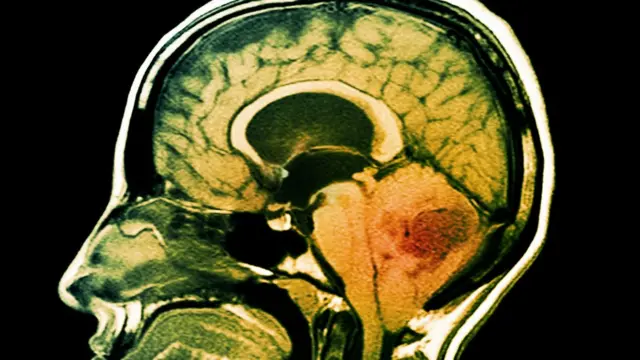

"Keunikannya bisa berkaitan dengan sel saraf... dan pada saat racun masuk ke sistem saraf, akan masuk ke sistem saraf besar... Dalam beberapa kasus digunakan untuk terapi kanker, karena bisa dengan cepat masuk ke sel saraf terutama di otak. Kasus di Amerika, misalnya adalah anak dua tahun dengan gejala kanker otak dan dipakai dokter untuk terapi dan bisa sampai ke otak."

Sumber gambar, Science Photo Library

"Beberapa ilmuwan menggunakan sebagai terapi kanker yang baru karena sifatnya cepat dan ukuran yang tak besar (molekulnya) dan bisa masuk dengan cepat ke bagian tubuh yang relatif susah dijangkau oleh obat yang berukuran lebih besar. Biasanya obat kanker itu molekulnya besar," kata Rama.

"Jadi pengobatan dengan racun kalajengking digunakan karena ukurannya lebih kecil yang susah ditembus oleh obat kanker konvensional."